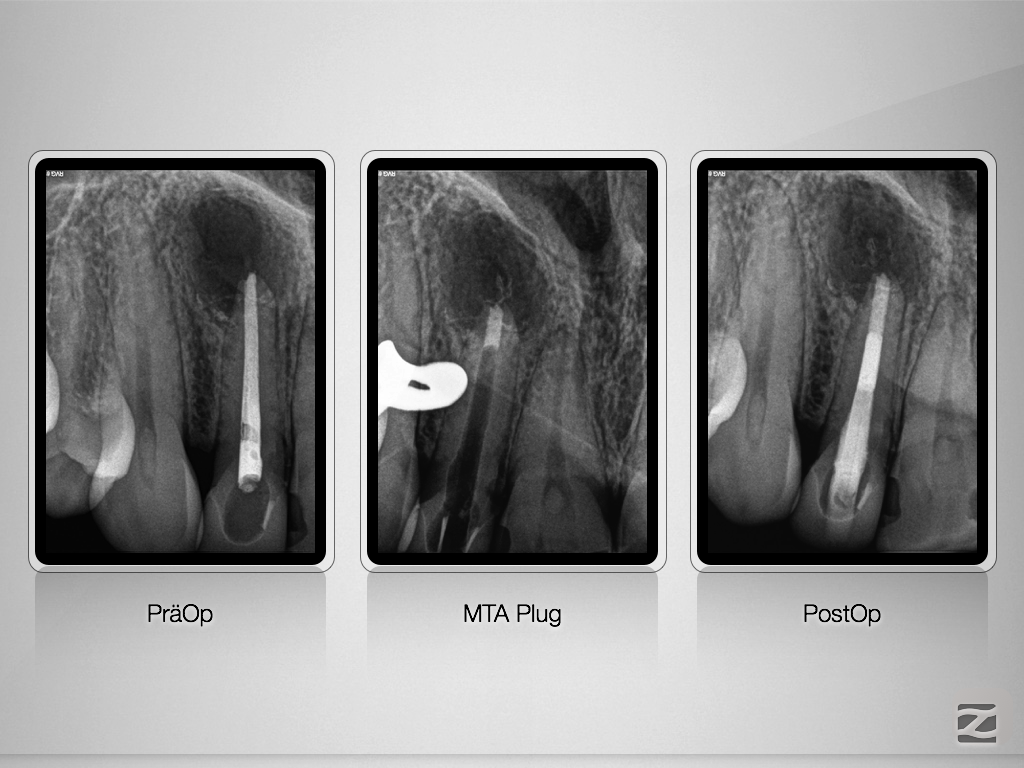

Immer schön skeptisch bleiben 2